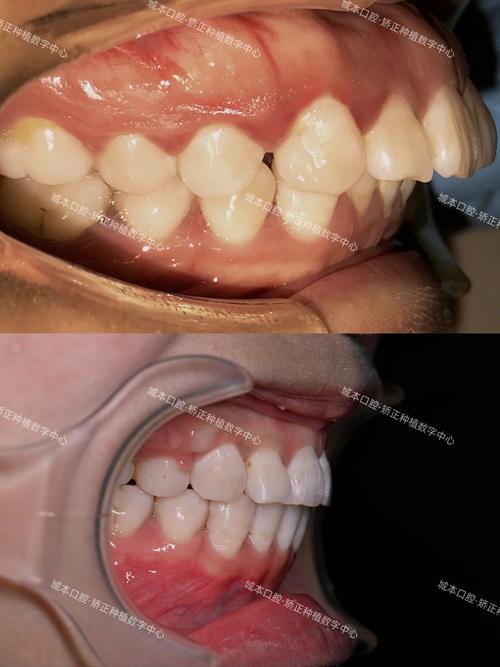

正畸牙齿牙龈脱离的临床表现及分级

牙龈脱离的症状和严重程度因人而异,轻度可能仅表现为轻微的牙龈退缩,重度则可能导致牙根大量暴露、牙齿松动甚至脱落,根据牙龈退缩量及附着丧失程度,临床可分为三级:

| 分级 | 牙龈退缩量(mm) | 附着丧失(mm) | 主要临床表现 |

|---|---|---|---|

| 轻度 | 1-2 | 1-2 | 牙根少量暴露,通常局限于前牙区,冷热刺激轻微敏感,牙龈颜色略苍白,无出血或偶有刷牙出血 |

| 中度 | 3-4 | 3-4 | 牙根暴露明显,可见牙本质黄色,牙齿对冷热酸甜刺激敏感,牙龈可能变薄、透明,刷牙易出血,牙间乳头可能出现萎缩 |

| 重度 | ≥5 | ≥5 | 牙根大面积暴露,部分可达牙根中1/3,牙齿敏感剧烈,甚至出现自发性疼痛,牙龈退缩导致牙缝变大,食物嵌塞频繁,牙齿可能出现Ⅰ-Ⅱ度松动 |

除上述分级表现外,部分患者还可能伴随牙龈颜色改变(从粉红色变为暗红色或苍白)、牙龈质地变脆、易出血,以及因牙根暴露导致的“牙变长”影响美观。